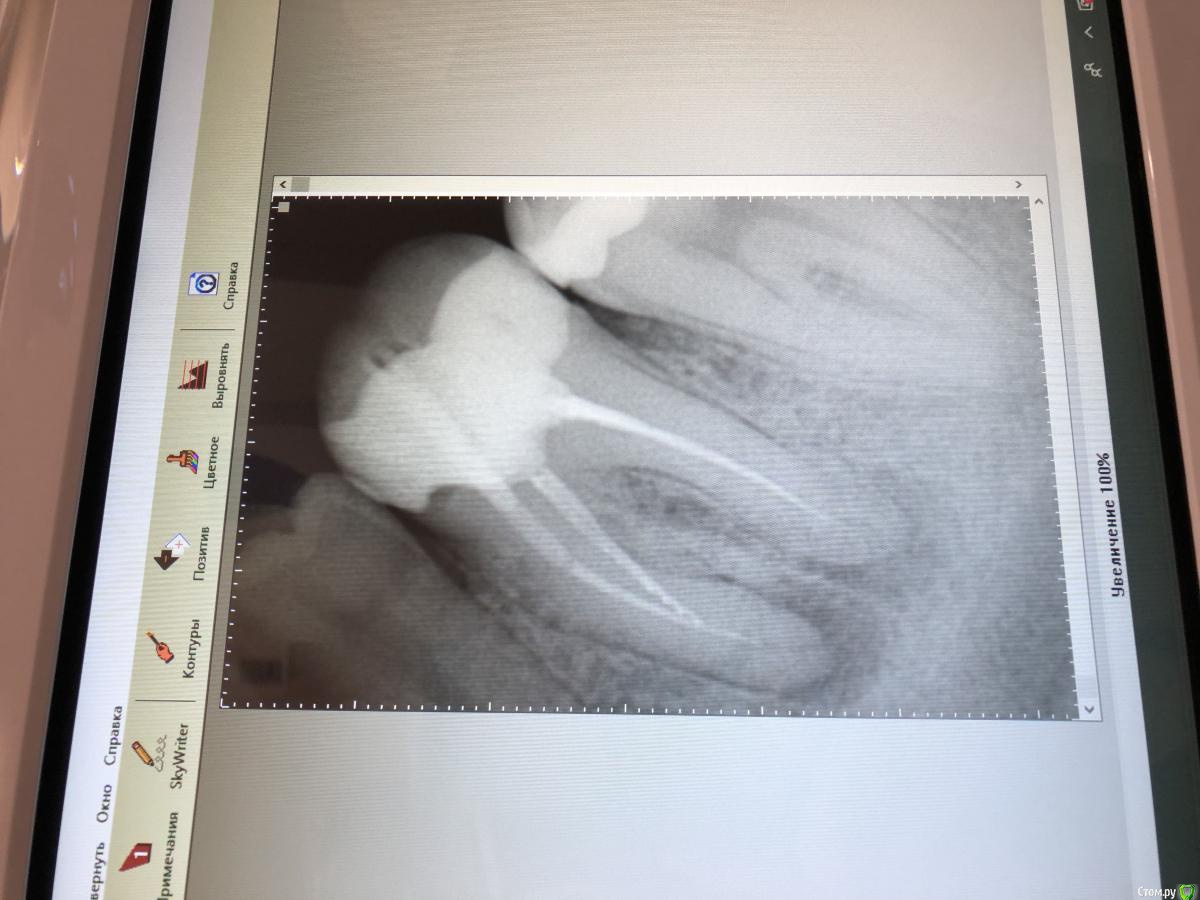

Марголин Опубликовано 1 марта, 2020 Автор Поделиться Опубликовано 1 марта, 2020 Снимок после перелечивания каналов и обхода инструмента Ссылка на комментарий

red_butler Опубликовано 1 марта, 2020 Поделиться Опубликовано 1 марта, 2020 На снимке все нормально. Скорее всего десна беспокоит Ссылка на комментарий